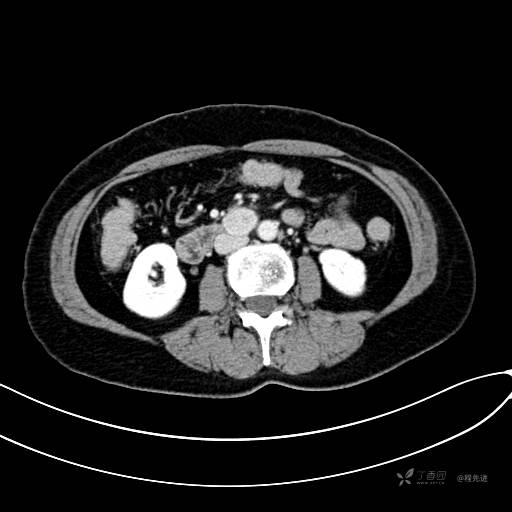

CT平扫